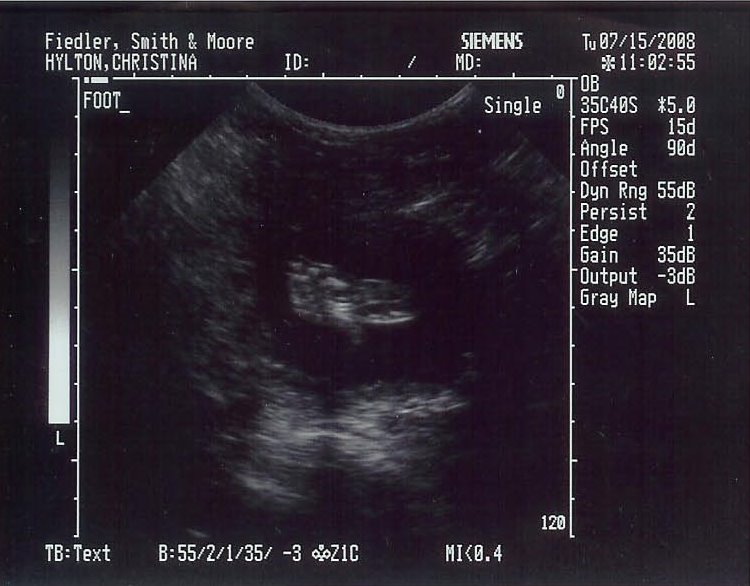

Unless you’ve caught a couple of my wife’s comments, or unless you know me personally, I’ve been keeping a secret from you — my wife and I are expecting our first child in November. Pictured above is one of his feet during the ultrasound the other day — yes, I said HIS. While this week has been full of gloom in my training and the past few months have been full of nothing but things going wrong in the job department, knowing that we are having a baby toward the end of this year has kept me going.

This week we found out that we’re having a boy — the full name is TBD. For the past few months both sides of our families have done the usual wishing that we were having a boy or a girl, while my wife and I have stayed silent in hopes that the baby is healthy. So far, things are looking good. And yes, we definitely know it’s a boy based on the money shot we saw the other day. I thought since this is a running blog it was only appropriate to post the foot shot. (Click here to check out my wife’s blog on the experience.)